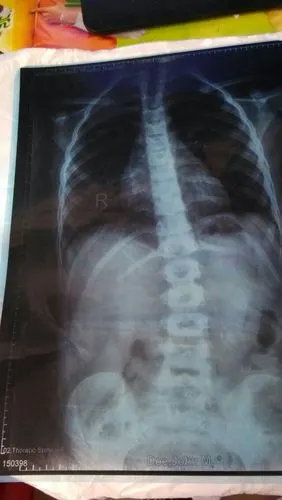

小海伦摔弯的脊柱

高低肩,背腰部肌肉不对称,遂至当地医院拍片发现脊柱侧弯约25

女儿8岁,在医院照x光片,发现胸腰段脊椎略侧突畸形,严重吗?